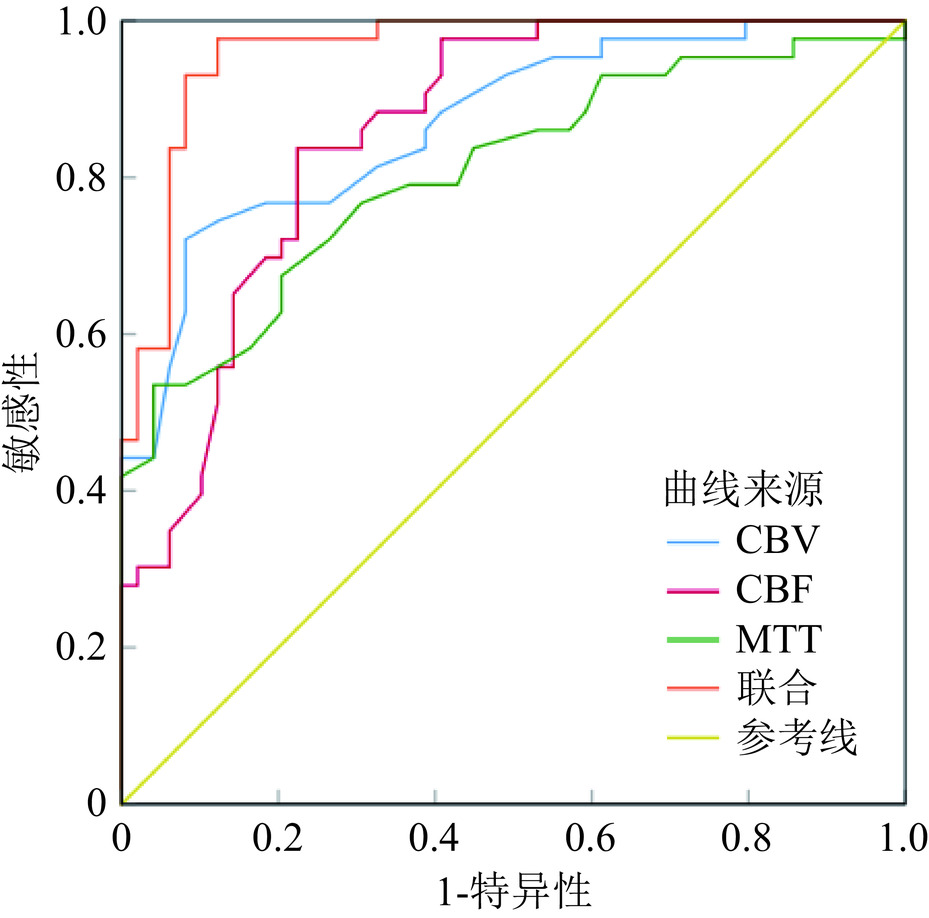

绘制ROC曲线(图2),结果显示,CBV、CBF、MTT诊断急性缺血性脑卒中患者侧支循环状态的AUC均>0.7,均有一定评估价值,且联合评估的AUC更高(Z=2.236、2.426、3.118,P=0.013、0.007、0.001)。见表4。

表 4 全脑CTP参数评估侧支循环状态的价值分析Table 4. Value analysis of whole brain CTP parameters in evaluating collateral circulation status参数 AUC AUC的95%CI P cut-off值 特异性 敏感度 约登指数 CBV 0.869 0.797-0.942 <0.001 2.60 mL/100 g 0.721 0.918 0.639 CBF 0.859 0.784-0.933 <0.001 29.90 mL/100 g/min 0.776 0.837 0.613 MTT 0.807 0.717-0.897 <0.001 4.35 0.694 0.767 0.461 联合 0.961 0.925-0.997 <0.001 − 0.878 0.977 0.855 3. 讨论

为进一步探究全脑CTP各参数对急性缺血性脑卒中患者侧支循环状态的评估价值,本研究行多因素Logistic分析控制其他变量的影响,结果显示,全脑CTP参数CBV、CBF、MTT均为急性缺血性脑卒中患者侧支循环状态的影响因素。且绘制ROC曲线得知,CBV、CBF、MTT评估侧支循环不良得到AUC均>0.7,有一定评估价值,而三者联合的AUC为0.970,评估价值更高。考虑原因在于,通过全脑CTP不仅具有优异的分辨率,显示大脑的缺血区域、梗死区域及血管狭窄或堵塞部位,且能够提供更为全面的、量化的血流信息,帮助临床准确评估大脑的血管状况,从而实现对侧支循环状态的准确判断,提高评估的灵敏度、准确度[19]。